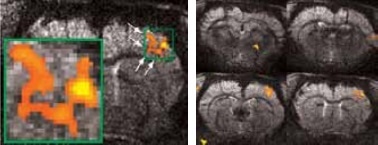

Using older DBX electronics and linear surface coils at 7.0 Tesla, BOLD contrast with 400 x 400 x 2000 μm3 resolution can be obtained. Combined with T2-maps, loss of functional activity and its instant recovery as well as stroke lesion (Figure 1) was defined[4,5]. A combination of faster AVANCE II readout electronics, quadrature surface coil, and higher field strength of 11.7 Tesla increased both resolution and SNR to less than 200 x 200 x 2000 μm3, which is more than sufficient to identify the tiny structures along the neuronal activity pathway like the thalamus and secondary somatosensory cortex S2 (Figure 2) with BOLD contrast.

BOLD activation at 11.7 Tesla using the quadrature surface coil with a resolution of (left) 300 x 300 x 2000 μm3 for high quality and (right) 150 x 200 x 2000 μm3 for high sensitivity.

Figure 2. BOLD activation at 11.7 Tesla using the quadrature surface coil with a resolution of (left) 300 x 300 x 2000 μm3 for high quality and (right) 150 x 200 x 2000 μm3 for high sensitivity. Image Credit: Bruker BioSpin Group